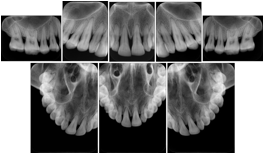

Intra-oral radiography typically involves acquisition of multiple images of various parts of the dentition. Many digital radiographic systems offer customized templates that are used for displaying the images in a study on the screen. These templates may also be referred to as mounts or view sets. The Structured Display Object represents a standard method of encoding and exchanging the layout and intended display of Structured Displays. A structured display object created in this manner could be stored with a study and exchanged with images to allow for complete reproduction of the original exam.

3. A dental provider wishes to capture a series of DICOM IO images for the patient’s dentition. The tooth morphology, teeth are divided into molars, premolars, canines and incisors, and a number of images for each jaw. The anatomic information was captured utilizing the triplet of schema. This standard code sequence is based on ISO 3950-2010, Dentistry - Designation system for teeth and areas of the oral cavity.

In most standard cases, images are oriented in structured layouts. These structured displays are useful to be shared between providers for reference purposes.